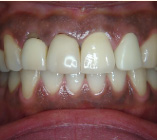

セラミック治療

こんな歯並びでもご心配なく。矯正という方法をとらなくても、ここまできれいに治せるんです。見た目だけでなく歯ブラシもやり易くなりました。笑顔に自信がつきますよ。

- 施術前

- 施術後